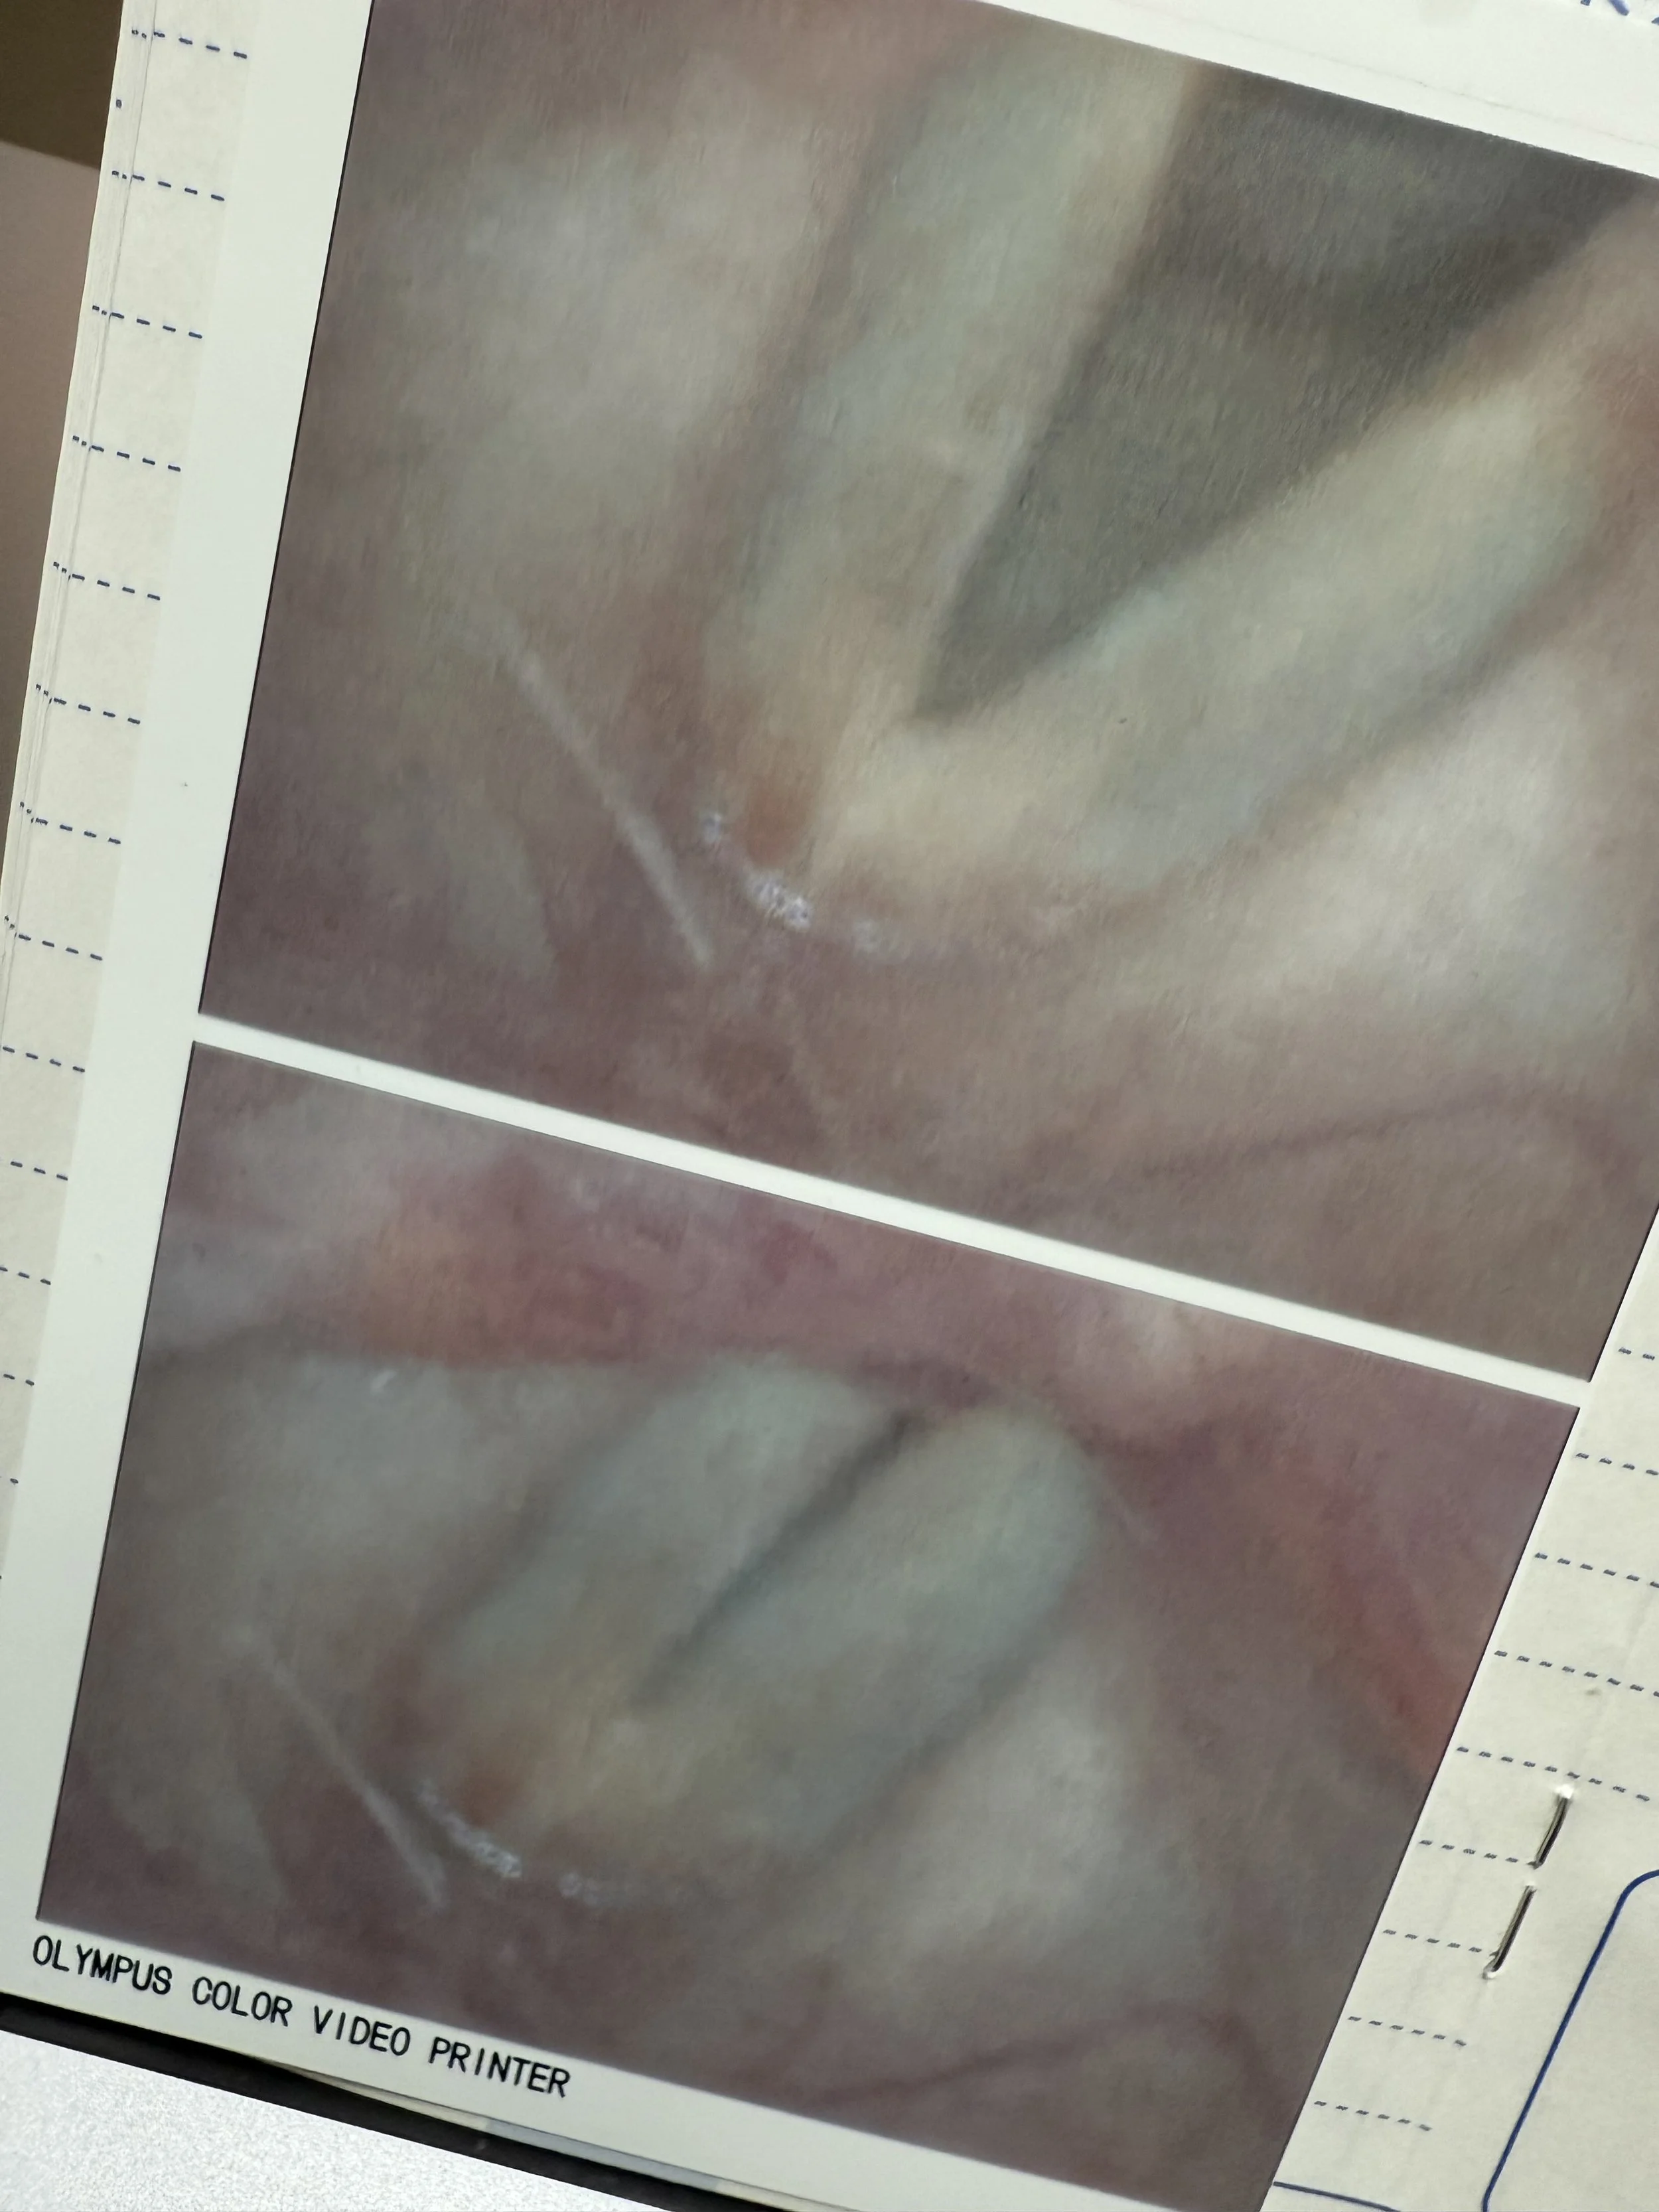

喉は大丈夫やった(声帯写真につき閲覧注意)

私の声帯は昨日より今日って感じで

良くなっていて嬉しい月曜日です

結節が悪化するとタチが悪いので

ホンマにビビってたけど良かったです

もうちょっとやけど治ってきてた

あと3日くらいで声帯の隙間が埋まります

(ピタッとくっついてなアカンのです)